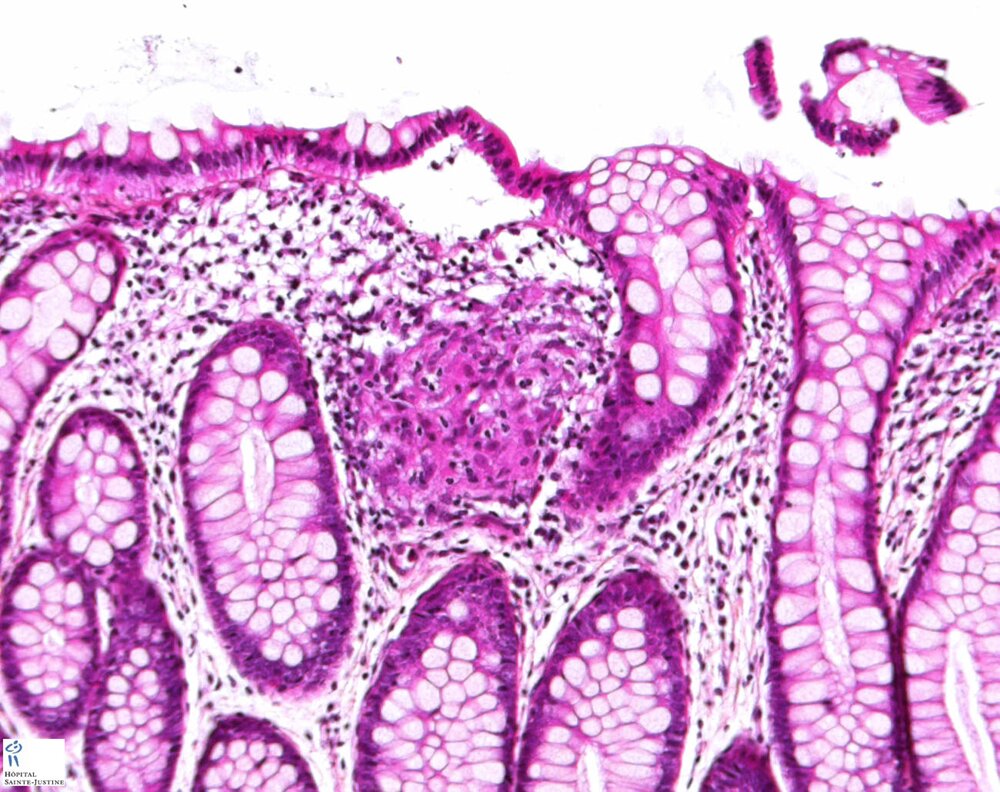

Etiology (exemples)

Crohn disease

tuberculous enterocolitis

digestive CGD (chronic granulomatous disease)

Hermansky-Pudlak syndrome